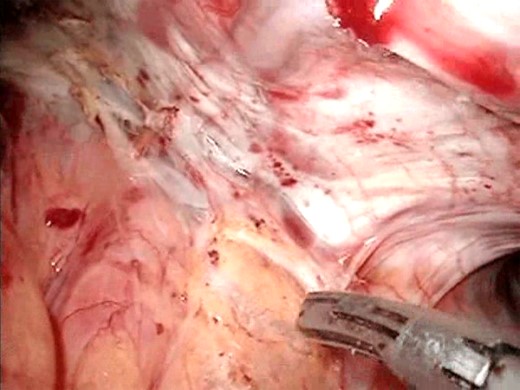

A 78-year-old Caucasian woman presented with recurrent dysphagia, slight tenderness in the epigastrium and substantial weight loss. Difficulty with solid food digestion and regurgitation were present for almost 10 years. The symptoms had exacerbated four months before intervention during which period the patient was fed through a nasogastric tube. CT scan, barium swallow (Fig. 1) and esophagogastroduodenoscopy showed a large mid-esophageal diverticulum. The neck of diverticulum was within 5 cm of the carina and was 4 cm wide. The diameter of the sac reached 10 cm, and narrow esophagogastric junction suggested achalasia, which was confirmed by manometry. The patient suffered a heart attack 3 years ago and has secondary dilatative ischemic cardiomyopathy. Due to cardiac co-morbidities, surgical intervention was graded as a high-risk procedure (ASA III), with patient’s quality of life being crucial in decision making. The patient was placed in supine position in reverse Trendelenburg with five ports placed as earlier described for transhiatal epiphrenic diverticula operations [7]. Throughout the procedure the esophagoscopic image was provided by an interventional gastroenterologist and dissection was performed under the guidance of both laparoscopic and endoscopic image (Fig. 2). This was essential due to a very narrow operating field and a lack of orientation points. The liver was retracted, and crura of the diaphragm were dissected with Ultracision (Ethicon Endo-Surgery Inc., Cincinnati, OH, USA) (Fig. 3), after which mediastinum was entered. The esophagus was bluntly dissected around its entire circumference and the gastroesophageal junction was encircled with an umbilical tape to ensure easier traction. The diverticulum was approached by both blunt dissection and electrocauterization. Resection of the wide neck of diverticulum was done with EndoGIA (Covidien, Mansfield, MA, USA) (Fig. 4). Another cartridge was used for dissection of the superior portion of the diverticulum. Possible air leakage was tested by irrigation of the field and was negative. Dissected diverticulum was withdrawn from the mediastinum and placed into an endobag. Heller myotomy was performed 5 cm orally and 2 cm distally from the gastroesophageal junction for reduction of achalasia. After the cruroplasty had been performed, the anterior fundus wall was sutured to the muscular edges of myotomy (Dor fundoplication) to prevent possible postoperative complications, such as gastroesophageal reflux disease (GERD). Operating time was 6 h, and the procedure went without any complications.

Gastroscopic guidance. This was needed for orientation within the mediastinum.